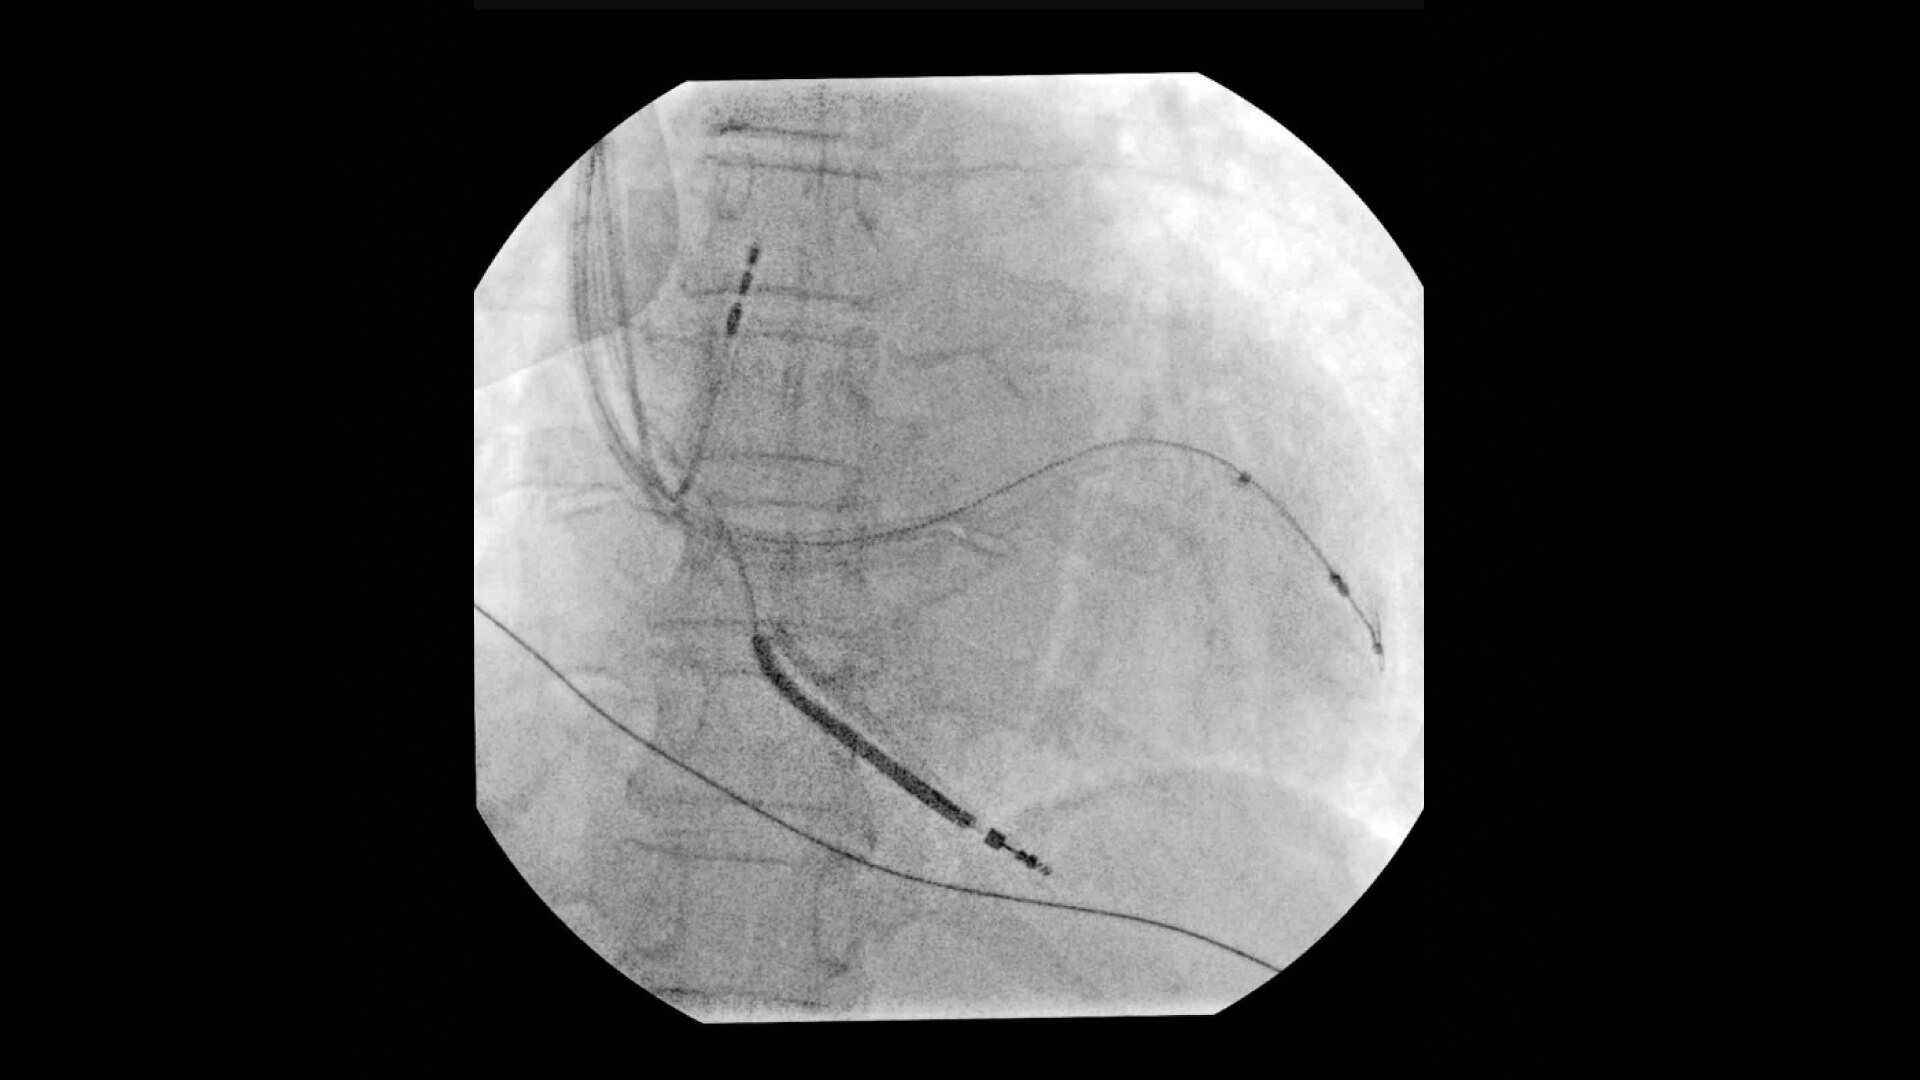

See 0.014” guidewires in thoracic region or wire leads when placing biventricular pacemakers with the OEC Elite CFD flat detector, image processing, and 4K display.

• Cardiac resynchronization therapy device implant

• Multisite pacemaker implant